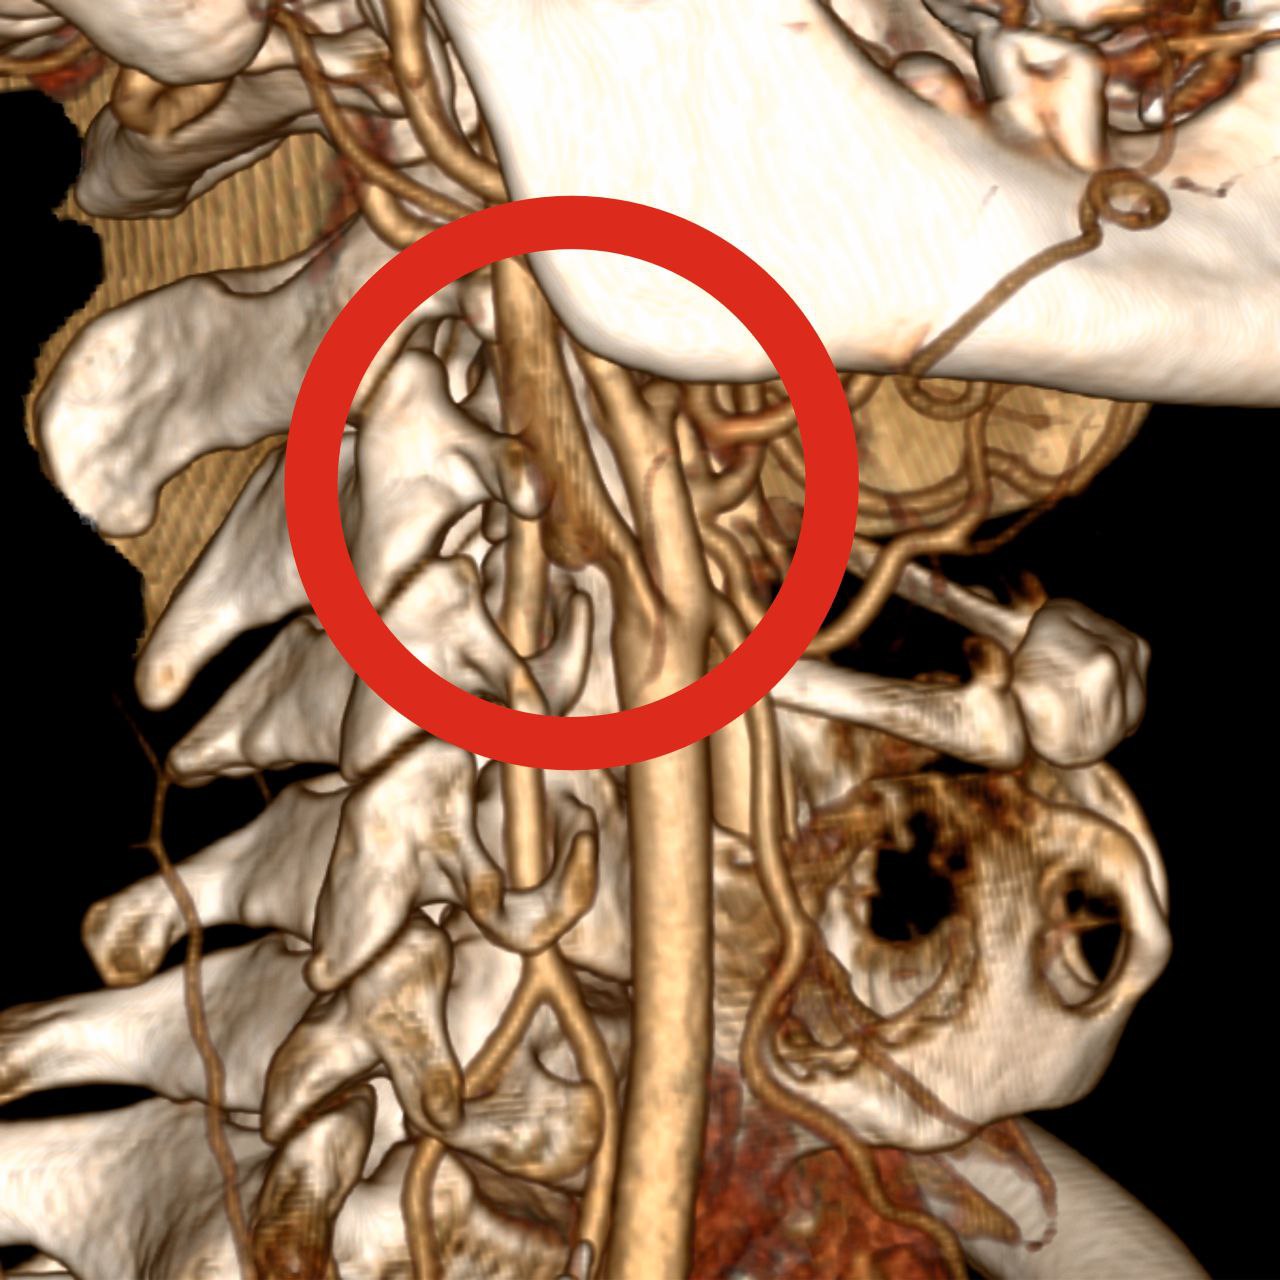

Сосудистыми нейрохирургами Алексеем Дмитриевым и Ильей Кораблёвым была выполнена экстренная операция - каротидная эндартерэктомия с удалением тромба из просвета правой внутренней сонной артерии. Благодаря проведенным манипуляциям тромб эвакуировался из сосуда под давлением крови. После этого хирурги удалили атеросклеротическую бляшку с восстановлением анатомии сосудов.